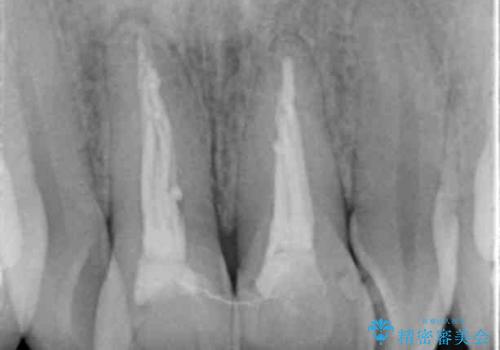

- 右上1+左上1/根管治療(保険),仮歯+ジルコニアクラウン(スペシャル):11,000円×2+130,000円×2 計282,000円(税別)費用は治療当時の料金となります

元々根管治療がされていたにも関わらず被せ物が作られておらず、このままではどんどん変色が進んでいってしまう状態でした。

歯をある程度削ることにはなりますが、被せ物にすることで歯の変色を隠し短期間でキレイな口元に仕上げることができました。